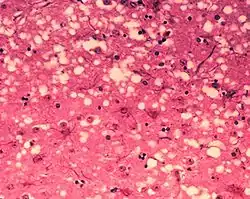

Пріони — це інфекційні білкові молекули, що не містять ДНК або РНК[52]. Вони спричиняють такі захворювання, як скрепі в овечок, губчастоподібна енцефалопатія великої рогатої худоби та хронічна слабкість (англ. chronic wasting disease) у оленевих. До пріонних хвороб людини відносять куру, хворобу Кройтцфельда — Якоба та синдром Герстмана — Штройслера — Шейнкера[53]. Пріони здатні стимулювати утворення власних копій. Пріонний білок здатен існувати у двох ізоформах: нормальній (PrPC) та пріонній (PrPSc). Пріонна форма, взаємодіючи з нормальним білком, сприяє його перетворенню в пріонну форму. Хоча пріони фундаментально відрізняються від вірусів і віроїдів, їх відкриття дає більше підстав повірити в те, що віруси могли піти від самовідтворюваних молекул[54].